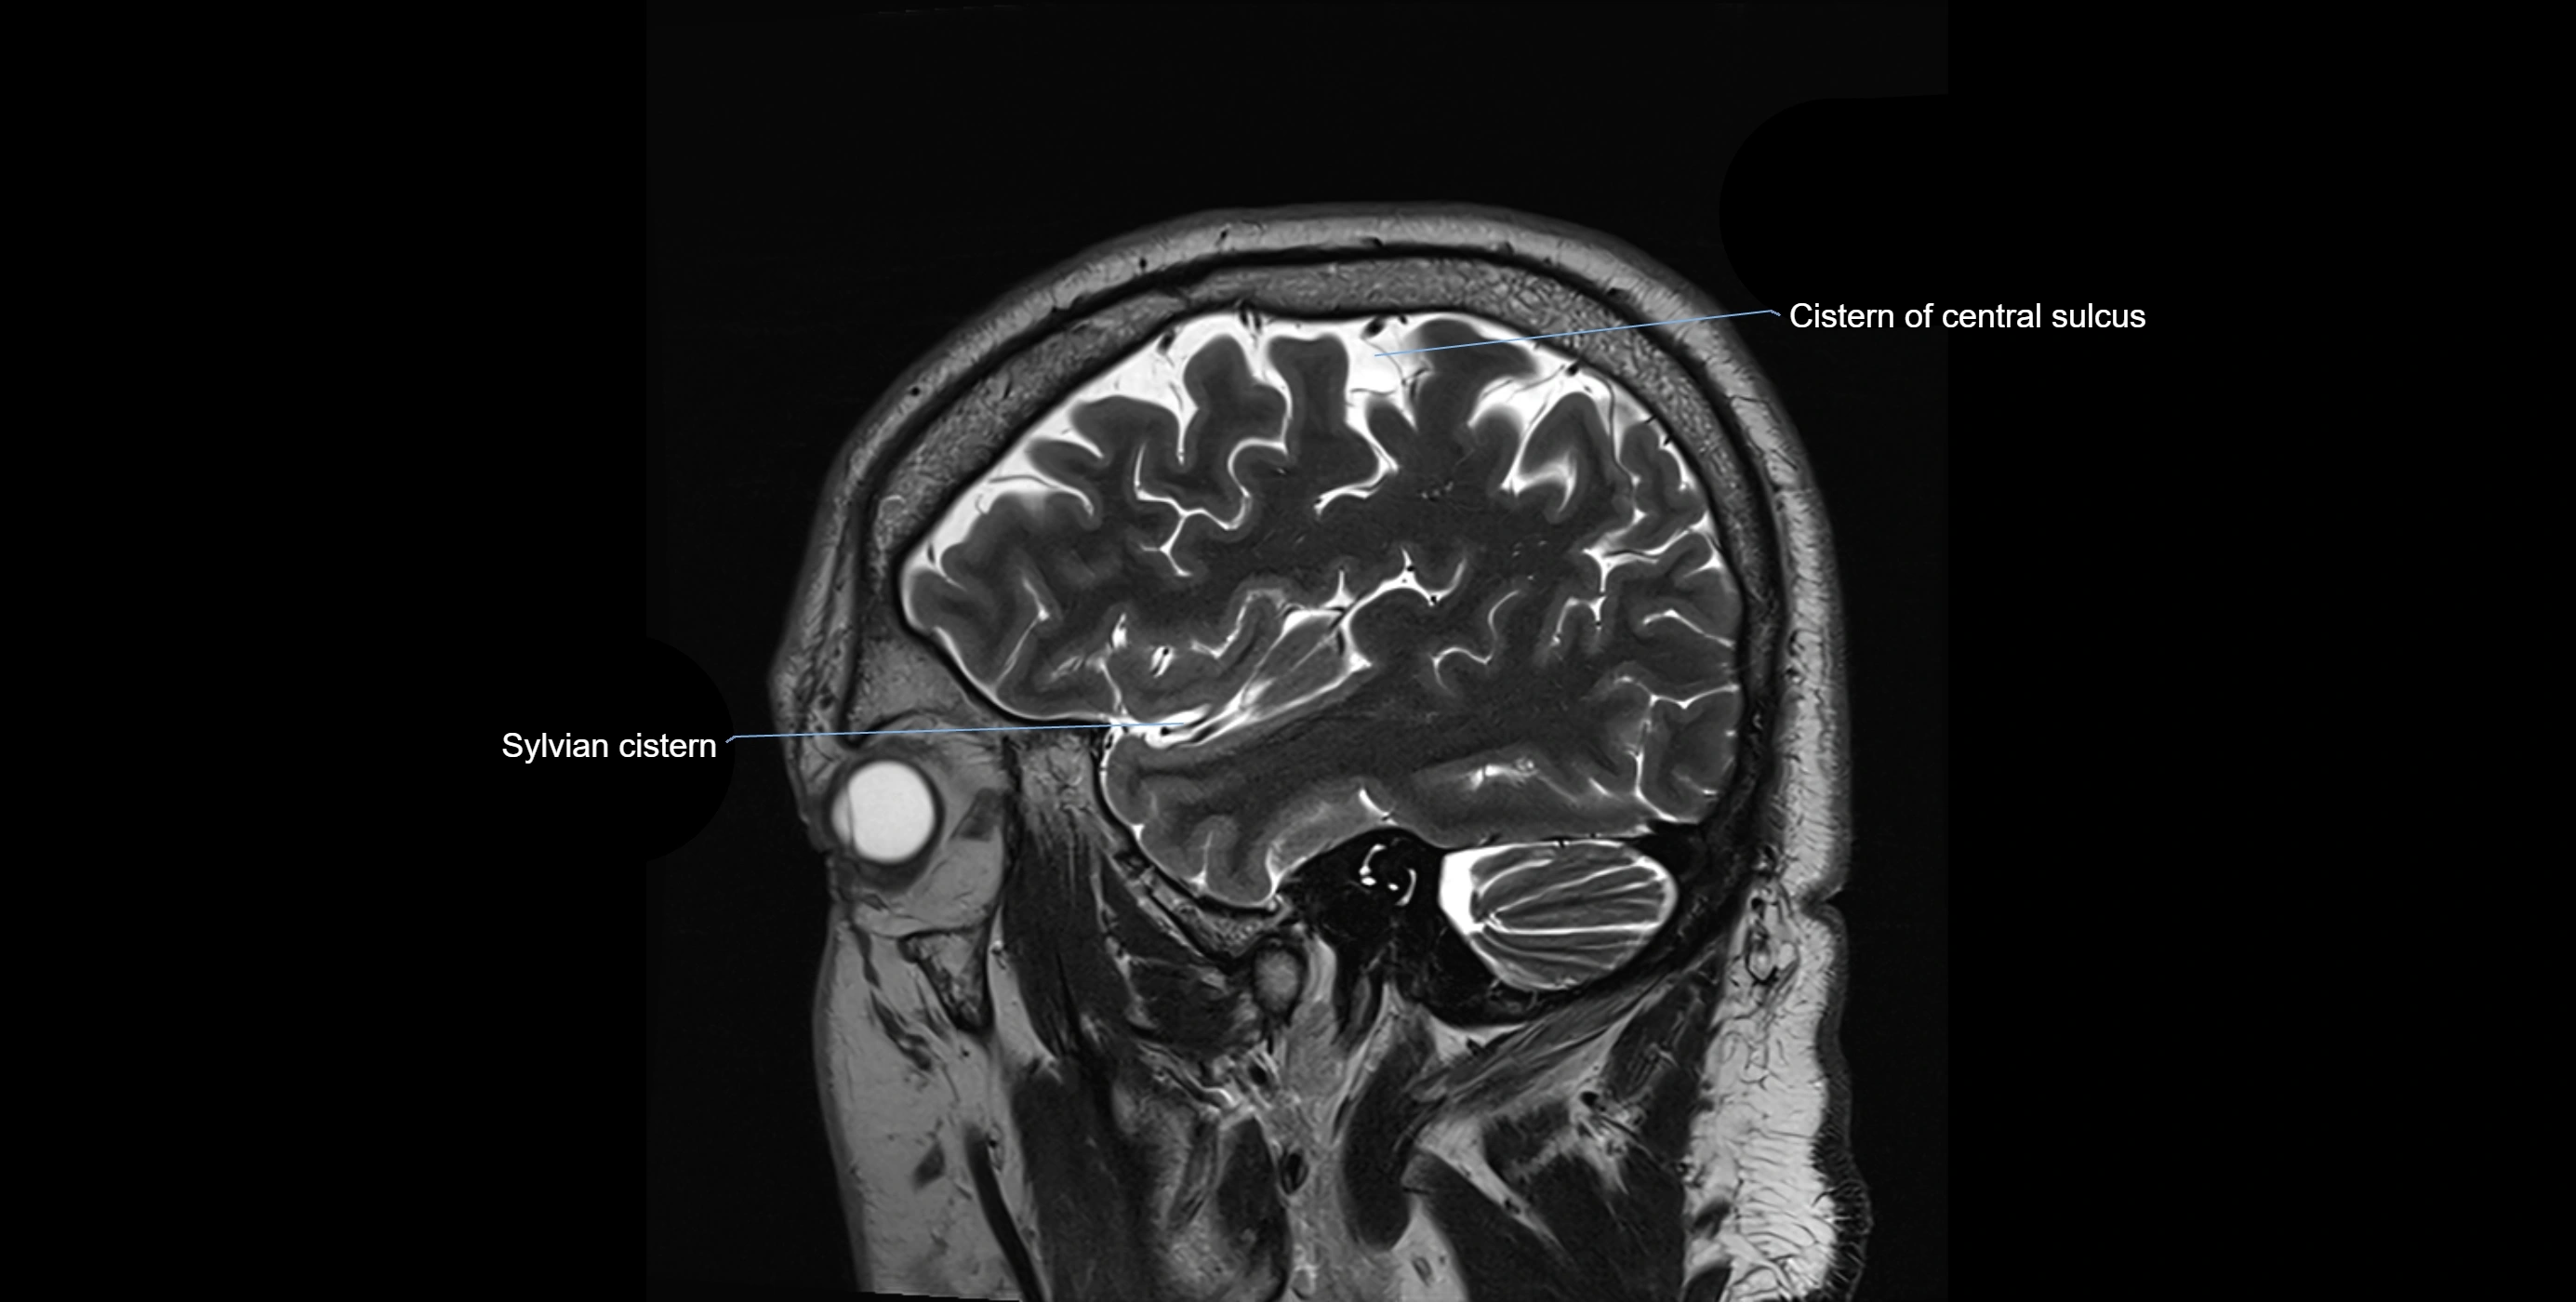

Ambient cistern

The ambient cistern is a paired, narrow, and elongated subarachnoid space located bilaterally along the lateral aspect of the midbrain. It serves as a conduit between the interpeduncular cistern anteriorly and the quadrigeminal cistern posteriorly. This cistern houses critical neurovascular structures, including parts of the posterior cerebral artery, superior cerebellar artery, trochlear nerve (cranial nerve IV), and the basal vein of Rosenthal. It plays an important role in the circulation of cerebrospinal fluid (CSF) and provides an anatomical corridor for various vessels and nerves passing around the midbrain.